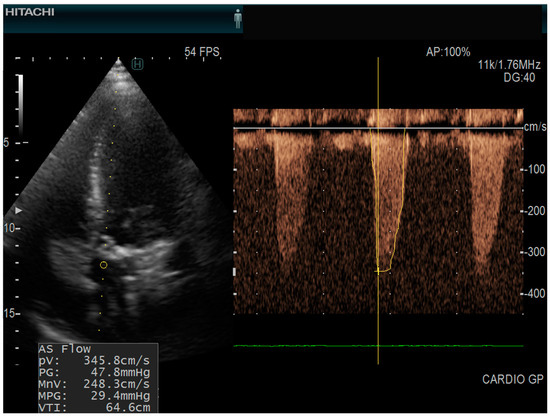

The types of valvular diseases are mentioned in Table 2. In our group, 7/45 patients (15.5%) had aortic stenosis (Figure 2). Patients with aortic stenosis had higher levels of dp-uc MGP; however, not statistically significant (4488.7 +/− 3244.97 vs. 2995.43 +/− 1791.58 pmol/L). The level of dp-uc MGP showed a weak direct statistically significant correlation with aortic flow speed (R = 0.3; p = 0.05). We could not find any statistically significant relationship between other cardiovascular disease markers (mitral, pulmonary, or tricuspid valvular parameters) and the level of dp-uc MGP.

Figure 2.

Echocardiography of a patient with aortic stenosis echocardiograph: Hitachi Arietta 65, apical five chamber view, continuous pulse wave doppler AS Flow = aortic stenosis flow; (PV = peak velocity; PG = peak gradient; MnV = mean velocity; MPG = mean pressure gradient; VTI = velocity time integral).